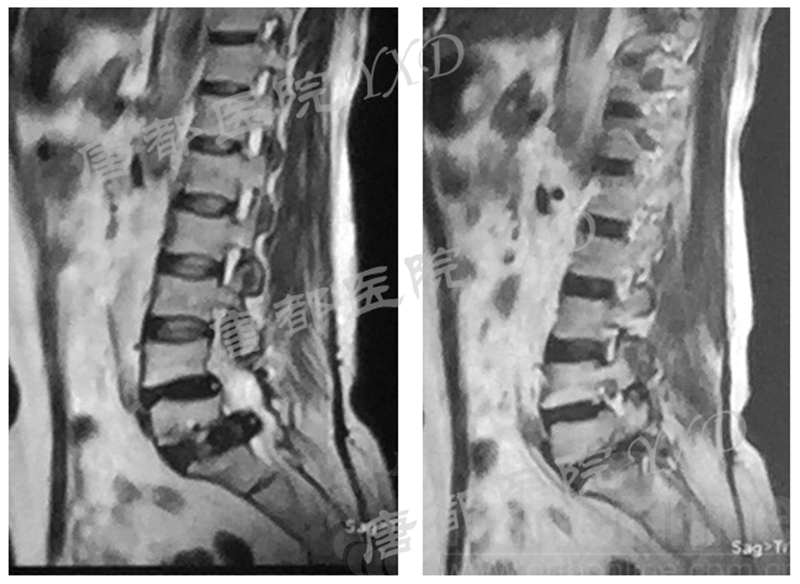

影像学检查:

诊断:腰椎间盘突出症术后复发

手术方案:显微镜辅助MI-TLIF腰椎翻修术